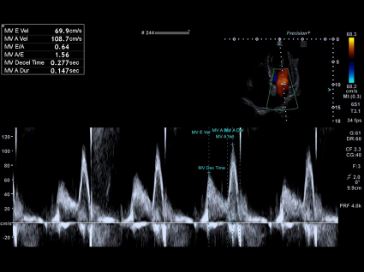

Автоматичне допплерівське стеження спрощує робочий процес за допомогою імпульсно-хвильових допплерівських (PWD) вимірювань.

Автоматизовані інструменти вимірювання та аналізу з підтримкою штучного інтелекту можуть допомогти підвищити точність, послідовність і швидкість досліджень. За допомогою Auto GLS (Quick Strain) комплексна оцінка лівого шлуночка або іншої камери серця, включаючи фракцію викиду та глобальну поздовжню деформацію, досягається простим вибором відповідного зображення.